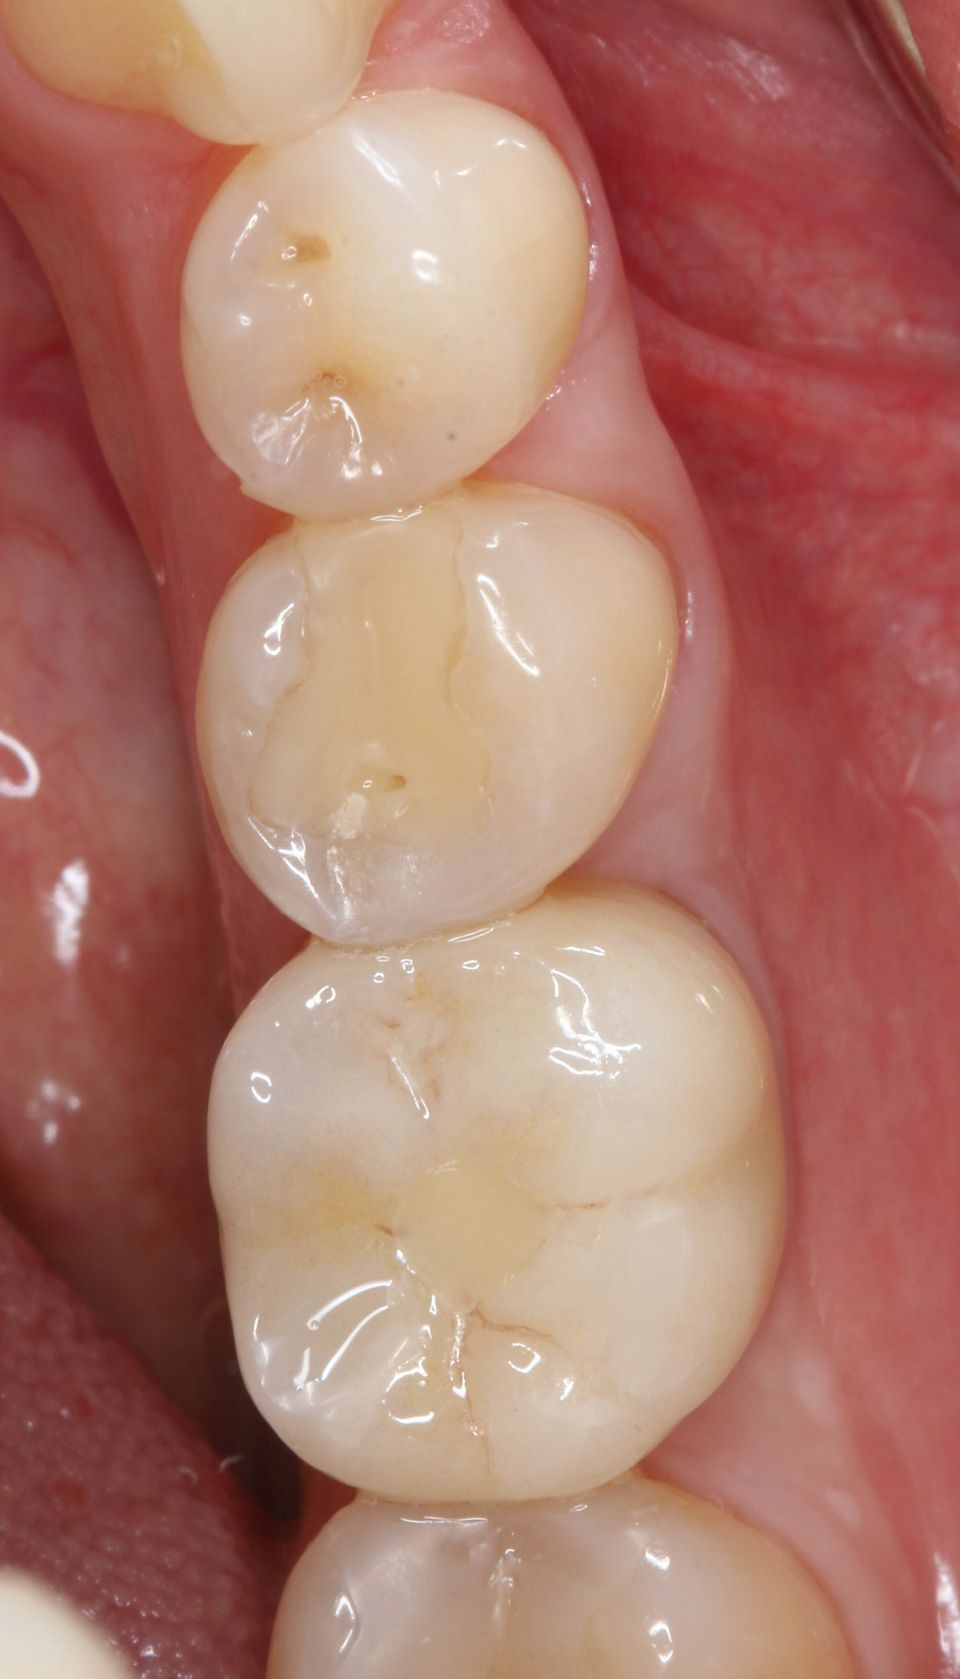

手术后一周,拆线(图11-12)。在同一次就诊时,拍摄了垂直牙科射线照片(图 13),显示种植体处于正确的修复位置。四个月后,愈合基台被移除。粘膜外观表明植入物周围有稳定且健康的软组织,具有足够的生物宽度和光滑的出现轮廓(图14-15)。取印模,一个月后,将最终的氧化锆陶瓷牙冠拧到种植体上(图 16-18)。